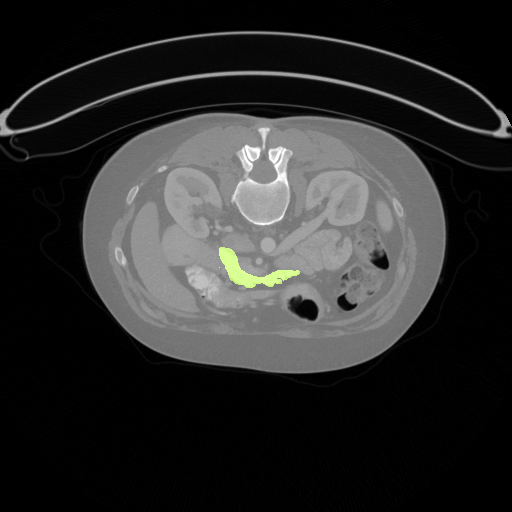

As an important and challenging problem in medical image analysis, pancreas segmentation over a CT volume is typically cast as a voxel-wise classification problem[1], which aims to assign semantic class labels to different CT image regions in a data-driven learning fashion. Usually, such a learning problem encounters numerous difficulties with small-sample-sized training, severe class imbalance, and background clutter with confusing distractions. As shown in Fig  1, a pancreas occupies less than 0.5% fraction of the entire CT volume, and meanwhile has a visually blurry inter-class boundary with respect to other tissues. Furthermore, the pancreas possesses the appearance properties of diverse shapes, various orientations, and different aspect ratios. Such challenging factors often makes the quality of data-driven learning degenerate to extremely biased results (e.g., eroded greatly by non-pancreas regions along with disrupted segmentation results). Therefore, the focus of this paper is on setting up an effective data-driven learning scheme for robust pancreas segmentation with a context-adaptive and environment-interactive pipeline.

Refer to caption

(a) 0.09%

(b) 0.76%

(c) 0.43%

(d) 0.19%

Figure 1: Illustration of challenges in pancreas segmentation. The images demonstrates the deformation of pancreas and its tininess in size. The pancreas zones (marked as green) vary in geometrical shape and angle. The smallest pancreas region can be less than 0.1%, and the largest part is no more than 0.8% of the whole slice. Better viewed in color.